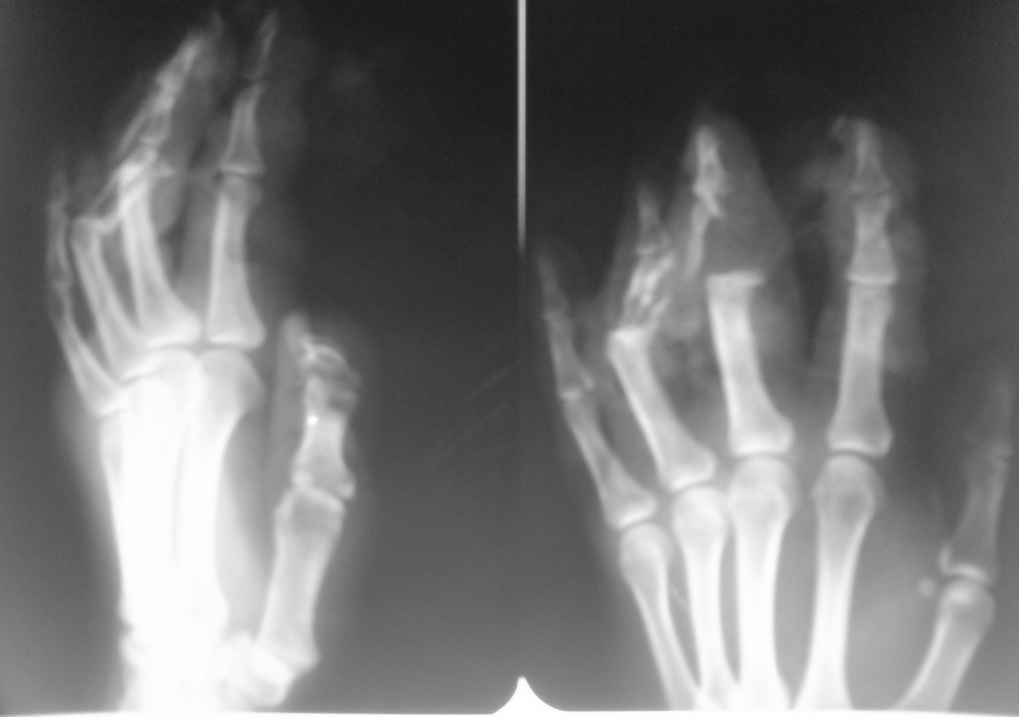

Пациентка 32 лет, врач-гинеколог. Травма электрорубанком 31.08.08

Диагноз: открытый оскольчатый перелом средних фаланг 3-4 пальцев левой кисти, травматический дефект средней фаланги 3-4 пальцев.

Травматический дефект кожи и сухожилий разгибателей 2,3,4 пальцев.

При поступлении выполненно ПХО ран, фиксация фаланг спицами в положении разгибания, синдактилия. Пласитка кожного дефекта полнослойным мостовидным лоскутом. Заживление ран первичное. Лоскут жизнеспособен.